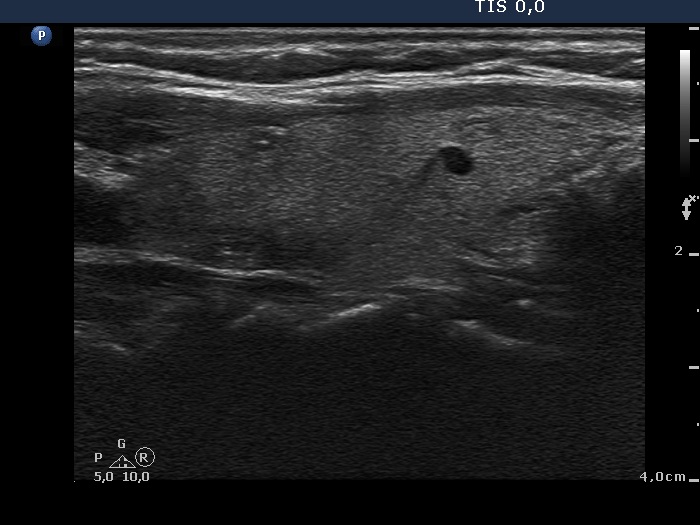

Subacute granulomatous de Quervain's thyroiditis - Case 6. (ultrasonographic picture 8)

Left lobe, longitudinal view. There are two discrete lesions presenting bright hyperechogenic granules which are probably microcalcifications.